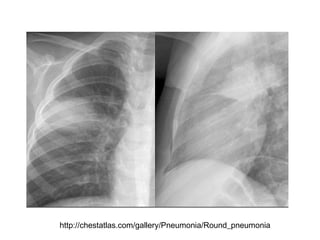

Manifestações radiográficas

Pneumonia por Mycoplasma, sorologia positiva

http://chestatlas.com/gallery/Pneumonia/Round_pneumonia

Pneumonia por Mycoplasma,sorologia positiva